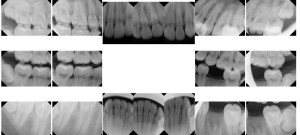

The common thread in most of the dental reports generated and produced to courts by ICE are scientifically inaccurate, show one-sided assumptions, use the wrong population data, exaggerate and sometimes are a complete lie. Among these is this redacted set of dental x-rays from a dentist in the Los Angeles metropolitan area. His ICE report stated this client had a high probability of being over the age of 18.

The x-rays do not even show the roots of the client’s wisdom teeth.